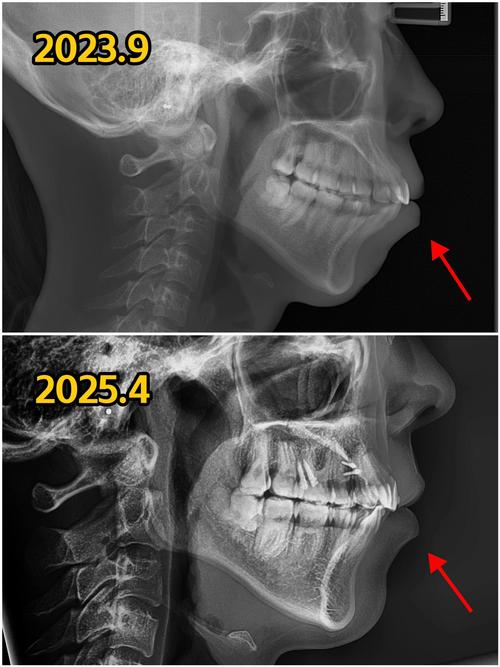

治疗结束后,拍片是判断矫正效果和长期稳定性的“金标准”,头颅侧位片对比术前,可明确SNA、SNB、ANB角是否恢复正常,面部突度是否协调;全景片观察牙根周围牙槽骨是否致密(提示牙周健康),牙列拥挤是否解除。

更重要的是,术后1-2年的定期拍片能监测复发风险:骨性III类患者若下颌角区域骨改建不足,可能出现下颌复发;II类患者若上颌骨内收后牙槽骨支持不足,可能导致牙齿反弹,通过影像学变化,医生可早期干预(如佩戴保持器、进行小范围调整),维持矫正效果。